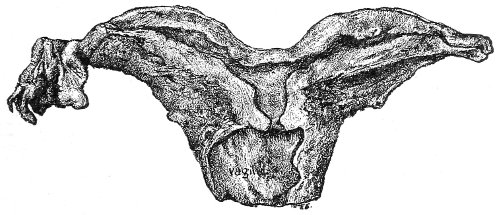

An accurate knowledge of the anatomy and mechanism of the female perineum is essential to an understanding of the nature and treatment of injuries to this structure. The anatomical structures lying between the anus behind and the symphysis pubis in front are those that most directly interest the gynecologist. Proceeding from 57 below upward, we find the following structures lying in superimposed planes: the skin, the superficial fascia, the deep layer of the superficial fascia, the transversus perinæi and the sphincter vaginæ muscles, the anterior layer of the triangular ligament, the posterior layer of the triangular ligament, the levator ani muscle (Fig. 19).

The vagina passes through these structures. They surround and support the ostium vaginæ as the fascia and muscles surround and support the opening of the rectum or the anus. The muscles and fasciæ are attached in the median line between the anus and the vagina, and therefore this part of the body, which is called the perineum, is supported or maintained in its 58 proper position by these various structures. The transversus perinæi arises from the ramus of the ischium and is inserted in the perineum. The bulbo-cavernosus, or sphincter vaginæ, arises in the perineum and is inserted in and about the clitoris. The inner fibers of the levator ani arise from the symphysis pubis and are inserted in the perineum and the lower part of the vagina (Fig. 20). When these muscles contract, their action, therefore, is to draw the perineum upward and forward. At the same time the anus is drawn upward and forward, and so also is the posterior margin of the ostium vaginæ and the lower portion of the posterior vaginal wall.

The vagina has no circular sphincter like the anus, but 59 the vaginal month is kept closed by the action of the transversus perinæi, sphincter vaginæ, and levator ani muscles, which draw the perineum forward, and thus keep the posterior vaginal wall in apposition with the anterior wall.

This sling of muscles and fascia, which surrounds and supports the opening of the vagina, may readily be felt in the nulliparous woman by introducing the finger in the vagina and pressing backward and outward toward the ischio-rectal fossa. We then feel plainly, immediately within the ostium vaginæ, a firm resisting band of tissue, apparently about half an inch broad, embracing the posterior portion of the lower vagina. This band is formed by the inner edges of the various muscles and planes of fascia that have been described.

The vagina extends, as a transverse slit in the pelvic floor, upward and backward, approximately in the direction 60 of a line drawn from the ostium vaginæ to the fifth sacral vertebra. It is approximately parallel with the conjugate of the brim, so that when the woman is erect the long axis of the vagina is inclined at an angle of 60° to the horizon. The vagina is not a vertical open tube: it is a slit in the pelvic floor, in health always closed by the accurate apposition of the anterior and posterior walls (Fig. 21). The anterior vaginal wall is about 2½ inches long in a vertical mesial line. The posterior vaginal wall is about 3½ inches long. The vaginal walls are triangular in shape, being broader above than below. The shape of the normal vagina at the pelvic outlet is shown by Fig. 23. The section here shows the vaginal 61 slit of the shape of the letter H. The portions of the slit extending backward and somewhat outward are called the vaginal sulci or furrows. They are directions of diminished resistance in which tears are liable to occur.

The injuries to the perineum that may result from childbirth are classified according to the position or the direction and extent of the laceration. They are as follows: slight median tear; median tear involving the sphincter ani; tear in one or both of the vaginal sulci; subcutaneous laceration of the muscles and fascia.